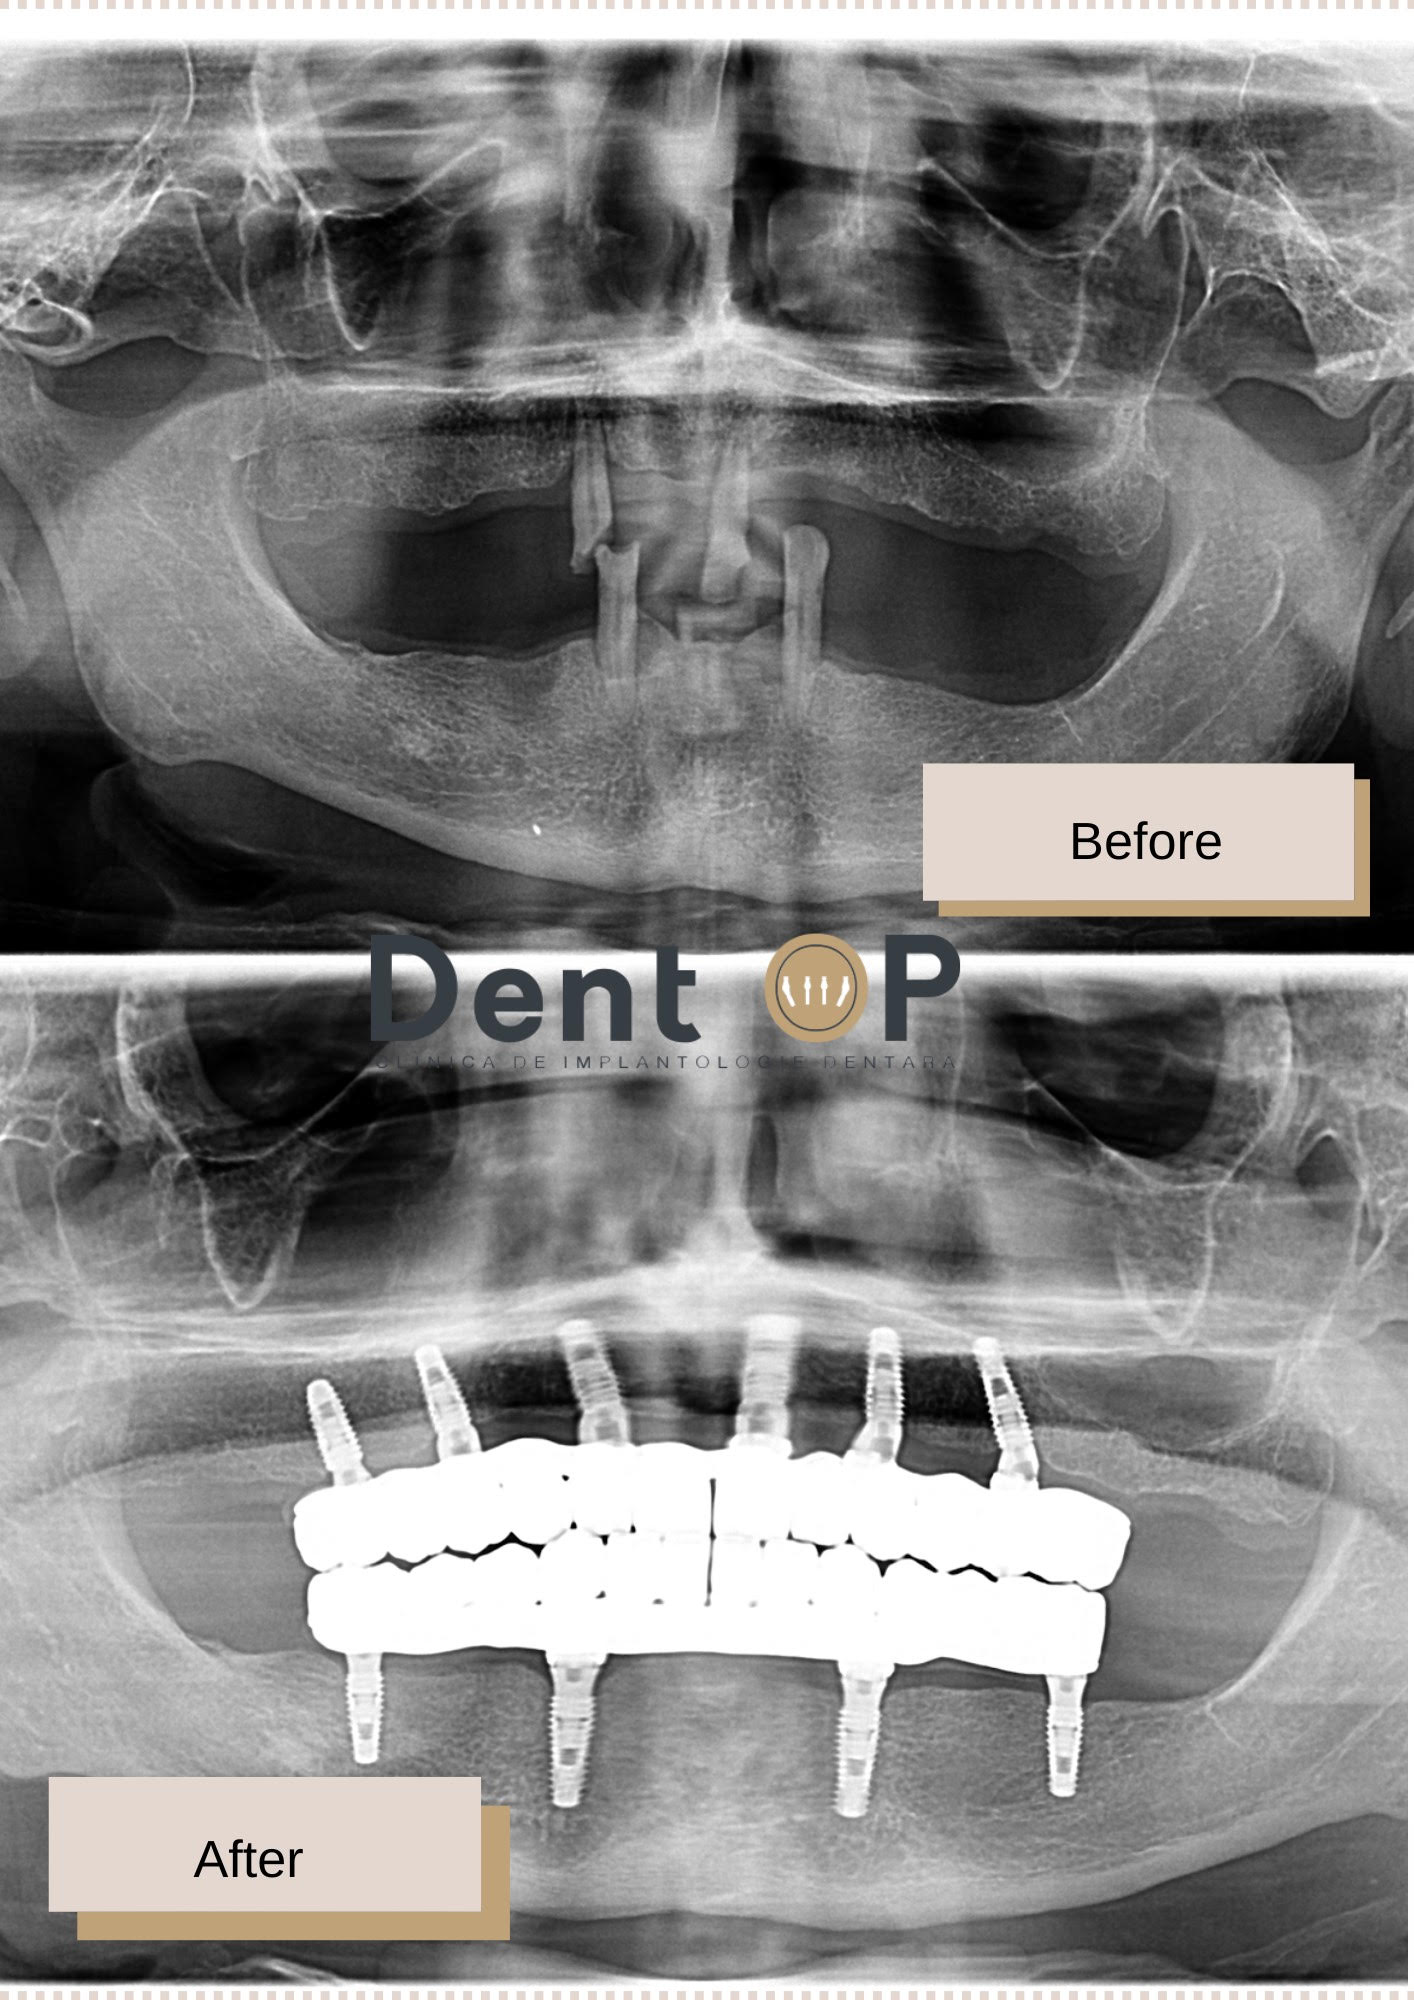

Domnul D. ne-a fost drag de la început și ne-am bucurat tare mult când am văzut pe chipul său bucuria de a putea zâmbi cu încredere. A venit cu doar 4 dinți rămași, caz pe care Dr Cazacu Corrado l-a preluat de la prima consultație.

În cadrul intervenției cu implanturi dentare, parte dintr-un plan de tratament propus de către Medicul Specialist Chirurgie Dento-Alveolară, domnul D. a primit 10 implanturi dentare într-o singură ședință. Pacientul nostru nu a simțit durere, dar nici frică datorită Sedării Conștiente.